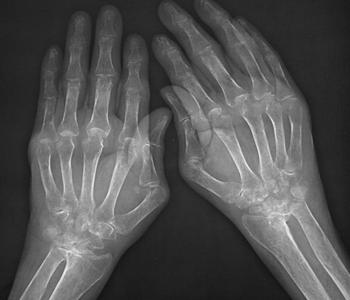

风湿性关节炎侵害关节的迹象有什么

1、多发性:风湿性关节炎常同时侵犯多个关节,呈对称性,局部有红、肿、热、痛及压痛。

2、大关节病变:常累及大关节,如膝、踝、肩、腕、髋、肘关节等。

3、游走性:一个关节炎症消退后,另一个关节接着发炎。

4、不留畸形:炎症消退后,关节功能完全恢复正常,不遗留关节畸形。>>>您现在病情是什么症状?点击免费咨询专家

不典型者仅有关节酸痛,其风湿炎症也可侵犯受阻小关节及脊柱,或仅限于单个关节。儿童患者关节炎症状多极轻微或仅限于一二个关节。成人患者的关节炎症状比较显著。关节炎程度与心脏损害轻重无明显关系。推荐阅读:初期的风湿性关节炎症状表现